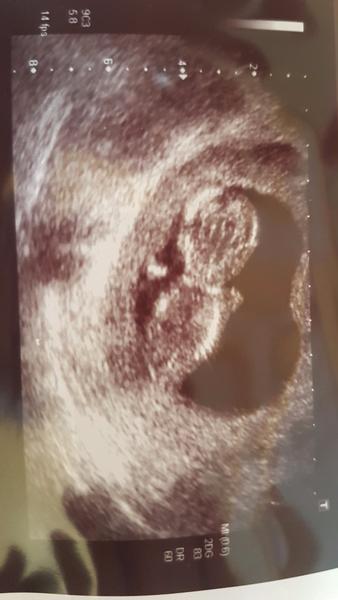

@juliane126 no mne merali babo naposledy na tom 3D v 13tt+6 a malo 76,1mm. Tak uvidime teda v tom 20tt 😉

@kattky a kedy ti 3D urcilo termin porodu? Mne 5.7.

Ja som mala byt tiez 13+6, ale zevraj uz 14+1. A malo uz cez 8, ale mne vravia zas, ze je moc velke. U nas vsetci chlapi maju tak 1,90, styria i k 2 metrom